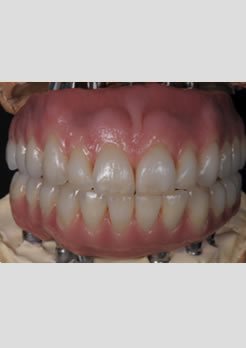

Próteses antes da instalação sobre o modelo de laboratório